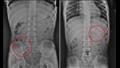

وكشفت فحوصات الأشعة السينية لصدر وبطن الطفل عن وجود قلم رصاص عالق في معدته، لذا أخبره الطبيب بالإكثار من السوائل، ، ولم يسمحوا له بتناول أي شيء سوى الموز لتسهيل عملية إزالة القلم من أمعائه.

أظهرت الأشعة السينية لاحقا أن قلم الرصاص تحرك من المعدة ليصل إلى "اللفائفي الأعوري"، وهو صمام عضلي يفصل بين الأمعاء الدقيقة والغليظة.